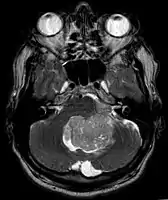

An ependymoma is a tumor that arises from the ependyma, a tissue of the central nervous system. Usually, in pediatric cases the location is intracranial, while in adults it is spinal. The common location of intracranial ependymomas is the fourth ventricle. Rarely, ependymomas can occur in the pelvic cavity.

Ependymomas make up about 5% of adult intracranial gliomas and up to 10% of childhood tumors of the central nervous system (CNS). Their occurrence seems to peak at age 5 years and then again at age 35. They develop from cells that line both the hollow cavities of the brain and the canal containing the spinal cord, but they usually arise from the floor of the fourth ventricle, situated in the lower back portion of the brain, where they may produce headache, nausea and vomiting by obstructing the flow of cerebrospinal fluid. This obstruction may also cause hydrocephalus. They may also arise in the spinal cord, conus medullaris and supratentorial locations.[6] Other symptoms can include (but are not limited to): loss of appetite, difficulty sleeping, temporary inability to distinguish colors, uncontrollable twitching, seeing vertical or horizontal lines when in bright light, and temporary memory loss. It should be remembered that these symptoms also are prevalent in many other illnesses not associated with ependymoma.